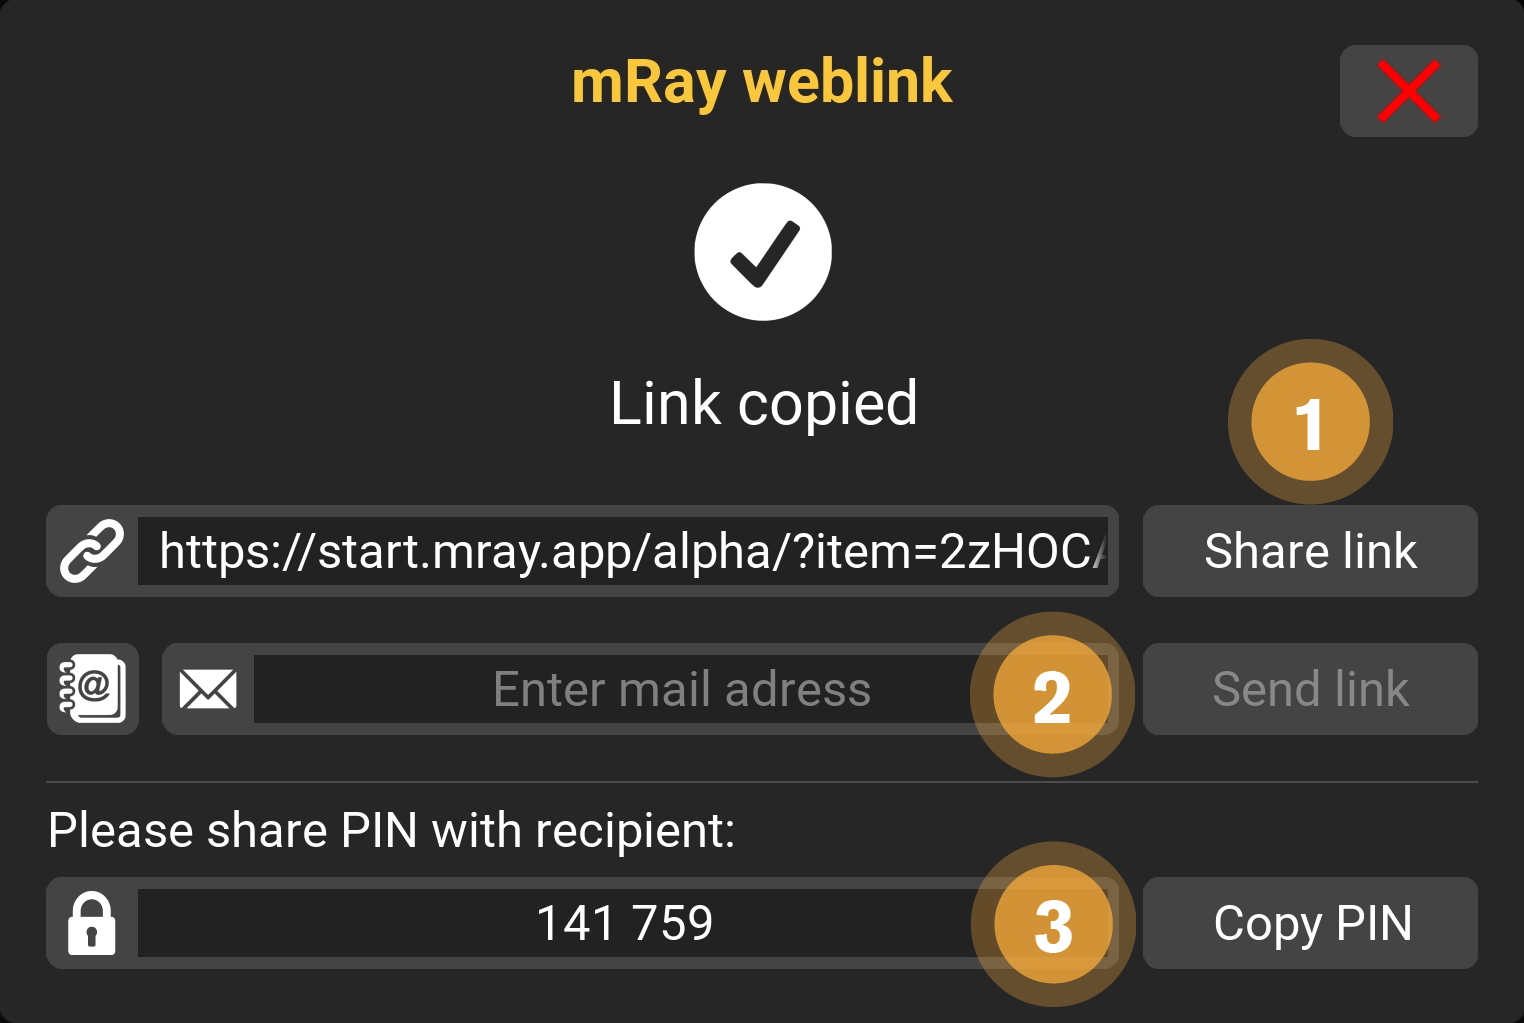

9.14. Link Einstellungen

Wenn Inhalte mit Links geteilt werden, stehen verschiedene Einstellungen zur Verfügung. Die Einstellungen und ihre Funktionen werden im Folgenden erklärt.

-

Sie können den Link im linken Textfeld manuell kopieren oder ihn, mit "Link teilen"("kopieren" auf dem Desktop), direkt in eine andere App teilen.

-

Alternativ zur ersten Variante können Sie hier die E-Mail Adresse des Empfängers eintragen.

-

Schicken Sie dem Empfänger diese PIN. Nur mit dieser können die Inhalte eingesehen werden.